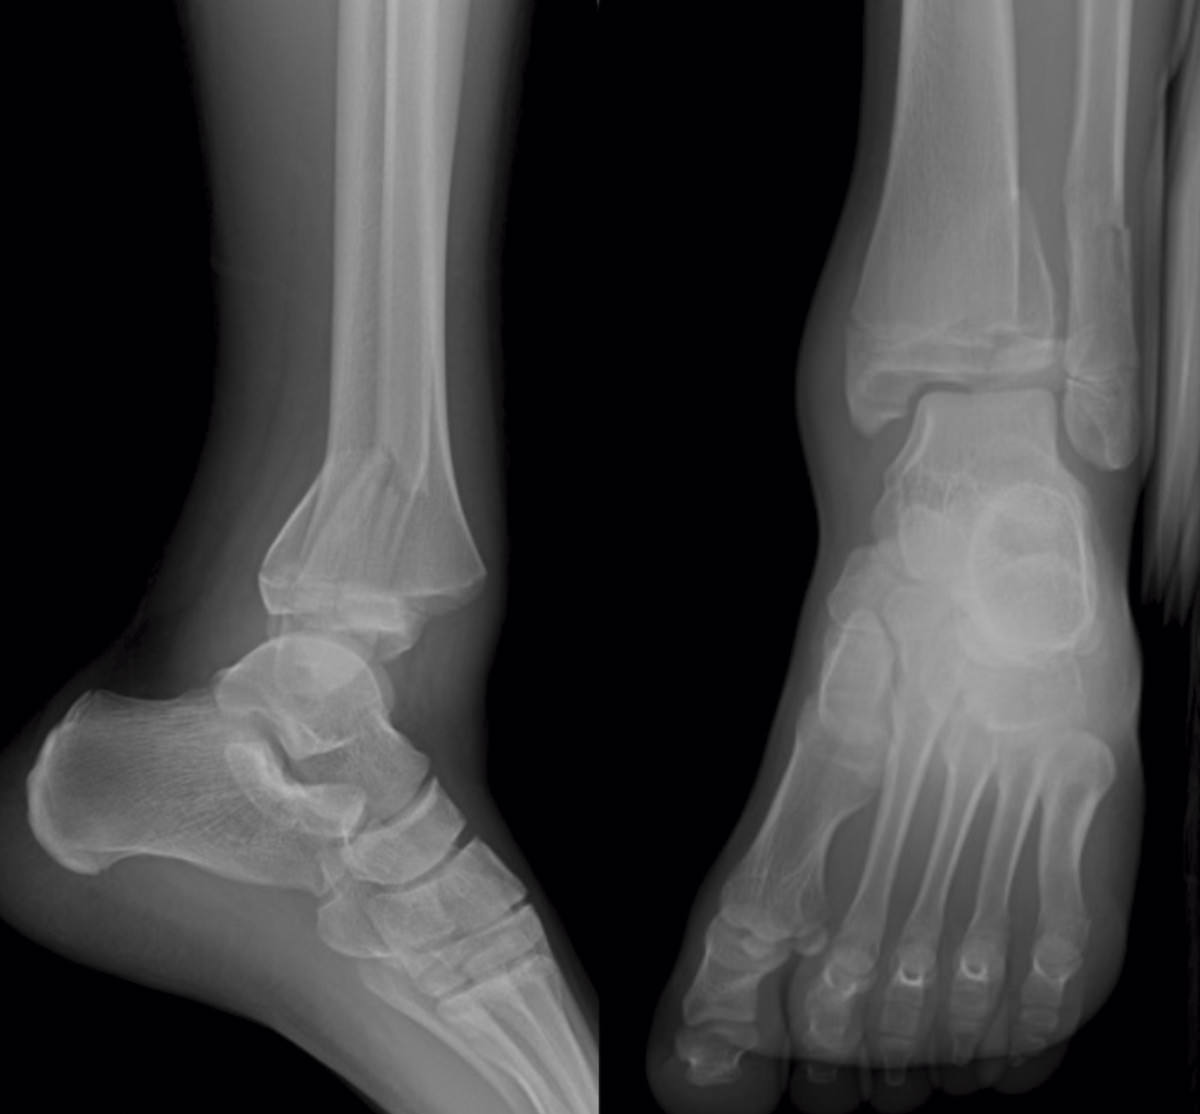

Se trata de un varón de 13 años de edad que acude a urgencias tras sufrir una caída y con eversión forzada del tobillo jugando al fútbol. A la exploración, presentaba inflamación en todo el tobillo izquierdo (región anterior y ambos maléolos) sin déficit neurovascular. En la radiografía simple se observó una fractura epifisiolisis de tipo IV (Figura 1).

Figura 1. Radiografía: epifisiolisis de tipo IV asociada a fractura de tercio distal de peroné.

La radiografía simple muestra una fractura de tipo III de Salter y Harris en la proyección anteroposterior y una de tipo II en la lateral con fragmento metafisario posterior. Pueden existir fracturas de peroné asociadas en un 24-50% de los casos(3)(4). Se han descrito numerosas variaciones incluyendo 2, 3 y 4 fragmentos.